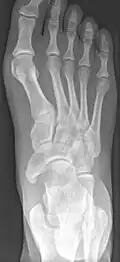

-

From left to right: Type 1, 2 and 3 -

Lateral projection of type 2 -

Type 2 -

Cornuate navicular bone -